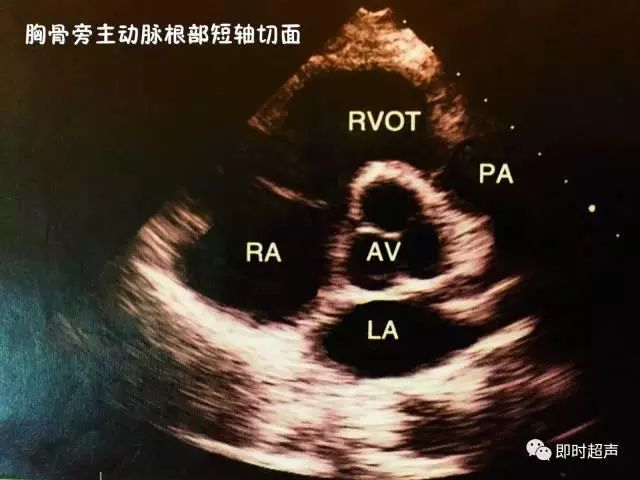

二、胸骨旁主动脉根部短轴切面

主要观察:主动脉机主动脉瓣、肺动脉及肺动脉瓣、右心室流出道和三尖瓣等的病变。